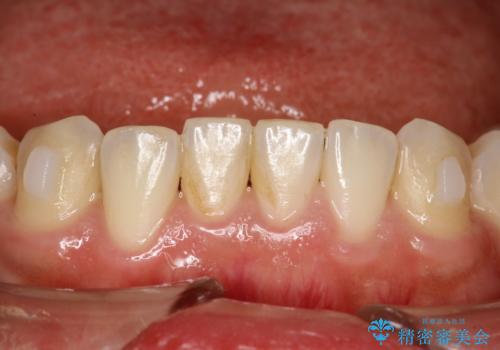

インビザライン中に歯の着色落としクリーニング PMTC

- インビザライン治療中に着色が気になるとのことでクリーニングを希望されました。PMTC30分コースを行いました。

インビザライン治療中には、歯の表面にアタッチメント(効率的に歯の移動をするもの)を設定します。そのため歯ブラシでは届きにくい細かい部分などに、歯石や着色がついてしまうことがあります。着色などを放置していると、着色なのか、虫歯なのかの判別もしずらく正確にお口の中の状態を診断できません。